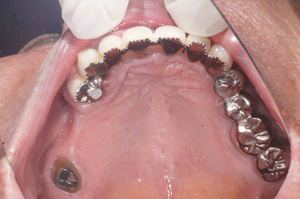

A.T‚³‚ñ@‚U‚QΠ —« Žå•w@Žèp“ú@‚Q‚O‚O‚X”N ‚UŒŽ‚Q‚R“úi‰Îj@ƒm[ƒxƒ‹ƒKƒCƒhŽg—p   Ö¬“à’ÁÖ@•¹—p

@@       ãŠ{   All on ‚V  ’x‰„‰×d @   Rpl Tapered Groovy Rp ‚P‚O mm~‚RA ‚P‚R mm~‚PA ‚P‚U mm~‚P@

@@ @@@    Nobel Speedy Groovy Shorty Rp~‚Q@@Nobel Speedy Groovy Rp ‚WD‚T mm~‚P

@      @   ‰ºŠ{  All on  ‚U  ‘¦Žž‰×d       Rpl Tapered Groovy Np ‚P‚O mm~‚Q        Bmk Rp‚RD‚V‚T mm  ‚WD‚T mm~‚QA@‚P‚O mm~‚Q

@           @– ƒ`ƒ^ƒ“ƒtƒŒ[ƒ€EƒJƒ“ƒ`ƒŒƒo[•â‹­i“Á’j‰„’·ƒuƒŠƒbƒW‚ÅÅI•â’Ô